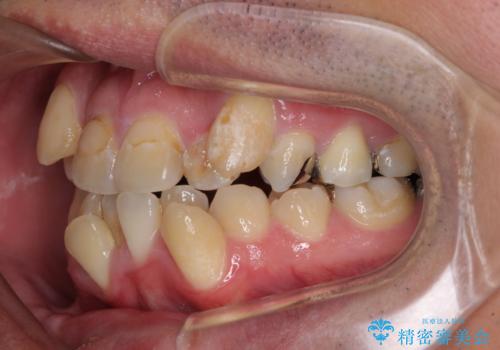

- 上下の八重歯やデコボコを気にして来院された患者様です。

上下ともに八重歯が顕著であったので、上下左右第一小臼歯4本を抜歯し、ワイヤー装置にて矯正治療を行うこととしました。

デコボコが強いことが原因で歯間部に汚れが溜まりやすい状態でしたが、矯正前にできる限り汚れが少なくなるようにブラッシングなどの指導を行い、口腔状態が改善された後にワイヤー装置を装着することとしました。